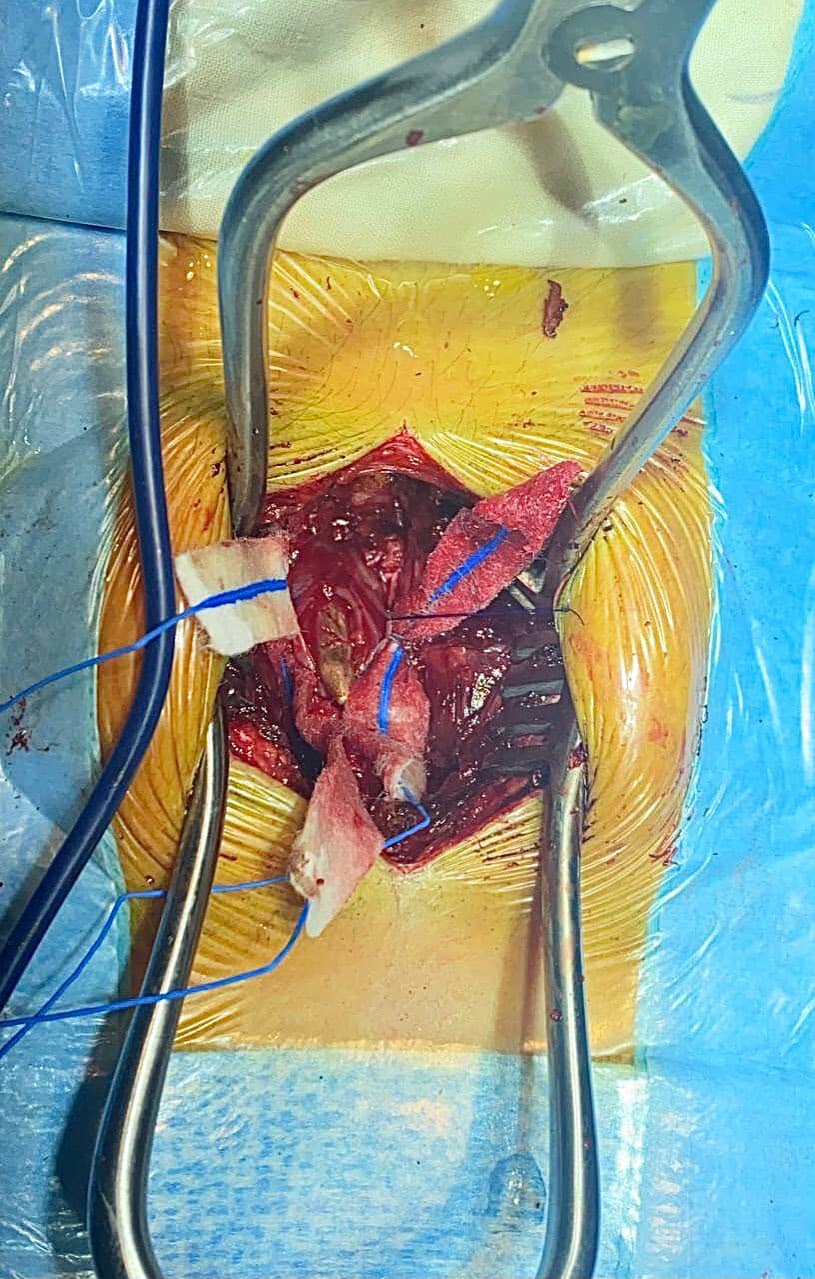

— Складність оперативного лікування в тому що куля у середені огорнута у так звану «біоплівку», в яку також були окутані нервові корінці, які виконують важливі неврологічні функції. Розмір яких у діаметрі 1-2 мм, і мають дуже ніжну структуру, — пояснюють в закладі.

Після видалення кулі нейрохірурги герметично зашили тверду мозкову оболонку із “тампонадою автожиром”. Після операції пацієнт знаходиться в задовільному стані, в нього немає неврологічного дефіциту. Нині він продовжує лікування в закладі. А після того на захисника чекає реабілітація.